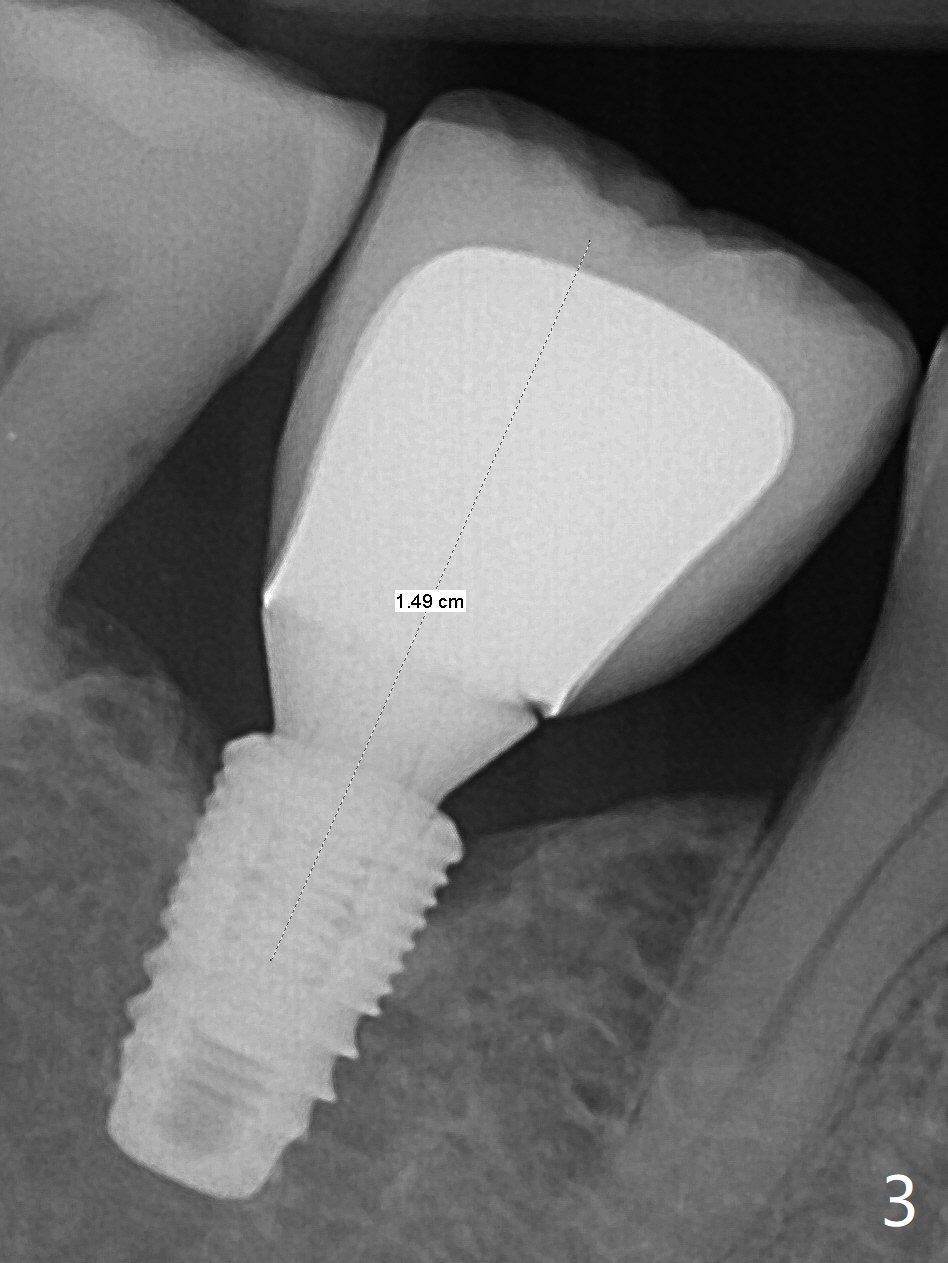

开场白病例

74岁男